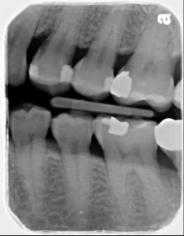

牙周初診時患者之口內觀。口內明顯牙菌斑及牙結石堆積。全口嚴重牙齦紅腫。治療前X光片。#37的近心側有較深的骨內缺損,剩餘齒槽骨高度只有20%。